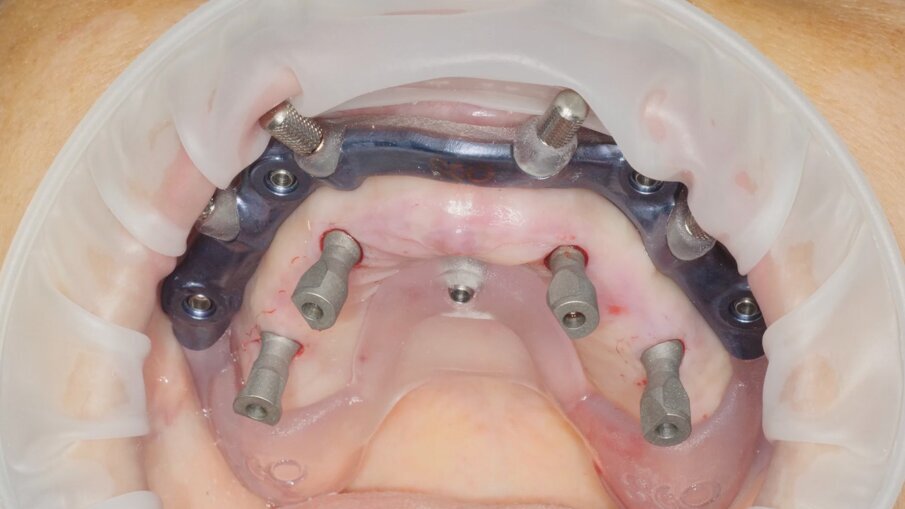

Il posizionamento implantare segue un ordine contrapposto, prestando attenzione nella fase di avvitamento a non arrivare subito a fine battuta sulla dima implantare (Figg. 14, 15). I mounter montati sugli impianti monofasici con MUA integrato devono essere inseriti all’interno delle cannule della dima implantare, prima di procedere a ricercare l’accoppiamento tra il mounter stesso e lo scasso sulla dima che permette l’accesso del cacciavite per il rilascio (Figg. 16-18). Questo accorgimento ci dà la conferma ulteriore del corretto posizionamento degli impianti con MUA integrato da 17° di inclinazione e non è previsto per i dispositivi con MUA integrato con inclinazione 0°. Una volta rimossi i mounter possiamo disancorare la dima chirurgica dalla dima base (Fig. 19). La Fig. 20 mostra l’emergenza della componente protesica integrata degli impianti attraverso la mucosa. Sui MUA vengono quindi posizionati gli abutment in titanio preparati dal tecnico che ha potuto seguire la chirurgia sul modello (Fig. 21).